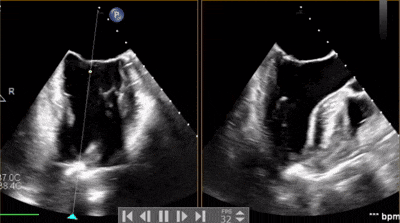

術(shù)前超聲

A3脫垂連枷(脫垂高度9mm,連枷高度:7mm),反流等級(jí)MR 4+(反流寬度11mm),有效瓣環(huán)面積MVA約6.3cm²。前瓣葉長(zhǎng)度23,后瓣葉長(zhǎng)度14.5mm,瓣環(huán)直徑AP 29mm。

術(shù)前術(shù)后對(duì)比

術(shù)前